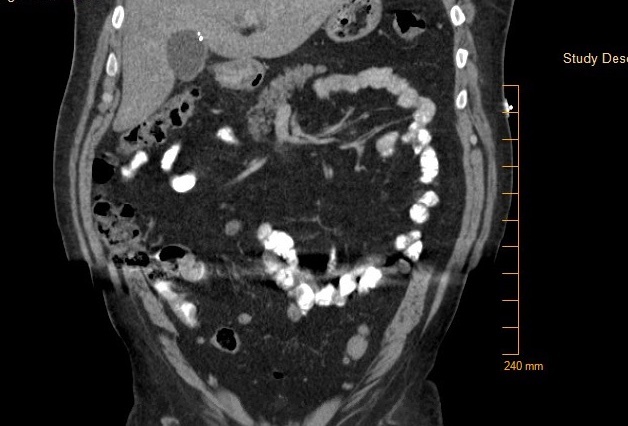

At his next visit with his PCP, however, he complained of pruritus, loss of appetite, 30 lb weight loss, weakness, increased yellowing of eyes, and worsening abdominal pain for 3 – 4 days. He was sent emergently to the ED, and a repeat CT scan of the abdomen/pelvis showed diffuse fatty infiltration of liver, mildly distended gallbladder with intra and extra hepatic biliary ductal dilatation and a common bile duct measuring up to 2 cm. No definitive filling defect was seen within the gallbladder. Ultrasound of the abdomen demonstrated dilated intrahepatic and extrahepatic ductal dilatation and uncomplicated small gallstones within the gallbladder but without choledocholithiasis or a discrete mass identified.

His laboratory values were significant for elevated total and direct bilirubin (22.4 and 15.9 mg/dl). Additional lab values include – an AST (137 U/L) and ALT (232 U/L), and an abnormally elevated Lipid panel with LDL (263 mg/dl), triglyceride (357 mg/dl), and total cholesterol (346 mg/dl). On day three of admission, the patient underwent an endoscopic retrograde cholangiopancreatography (ERCP) with findings significant for multiple gallstones in the common bile duct (Fig. 1 - 4) consistent with Mirizzi syndrome.

Mirizzi syndrome is obstruction of the common hepatic duct from a stone impacted on the gallbladder infundibulum or cystic duct remnant. It has been classified into five variants (Table 1) based on the Csendes 2007 classification.1 It usually presents with right upper quadrant pain, with or without jaundice and fever.2 The most commonly used studies for diagnosing Mirizzi syndrome are the ultrasound, computed tomography (CT), magnetic resonance cholangiopancreatography (MRCP) but the endoscopic retrograde cholangiopancreatography (ERCP) is the most sensitive.3 It is reported to have a 100% sensitivity,3 and as seen in this case can be diagnostic for Mirizzi syndrome.